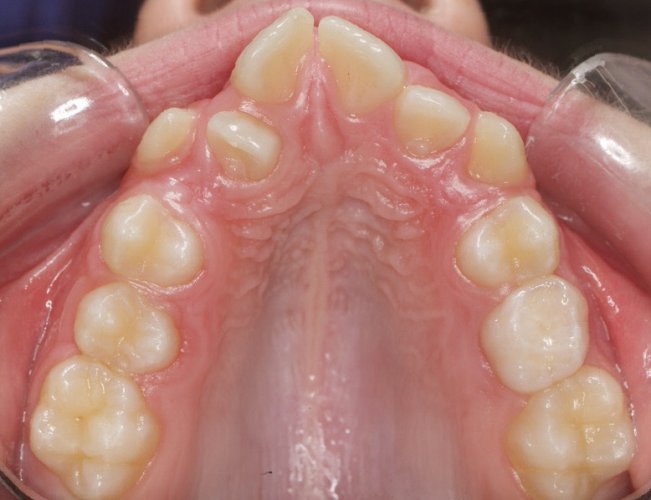

El paciente A.J. de 11 años, acude a nuestra consulta con apiñamiento maxilar importante. El canino lateral (12) está en mordida cruzada. Presenta una Clase II molar y canina, y la línea media está desviada. Se realizó un tratamiento con brackets autoligables metálicos de smartclip 022. La duración del tratamiento fue de 22 meses.

El paciente actualmente ha terminado el tratamiento con brackets y lleva una contención fija de 2-2 en maxilar y 3-3 en mandibular; para complementar también lleva una férula ESSIX durante la noche.

INICIO FINAL